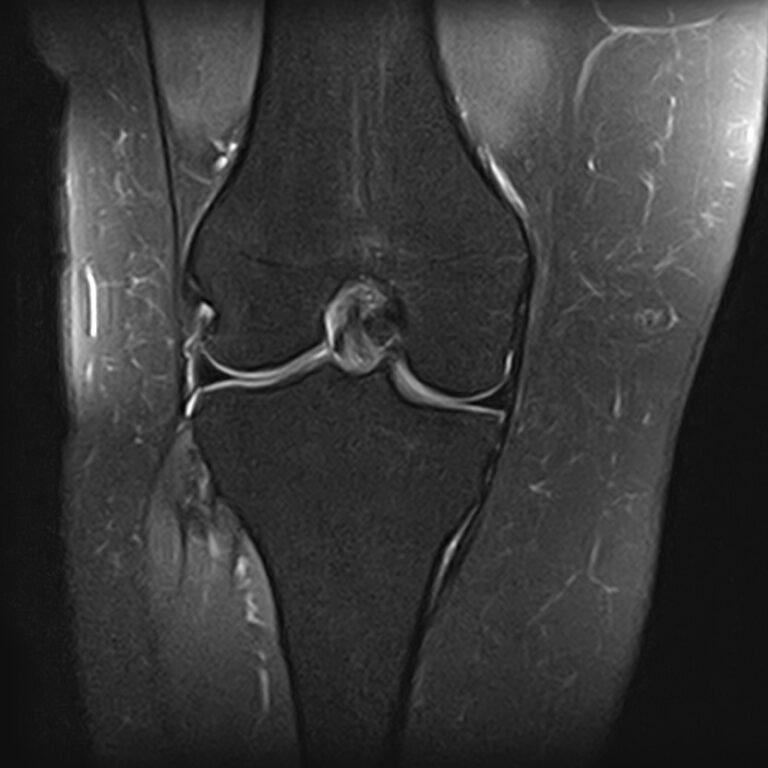

Магнитно-резонансная томография является высокоинформативным методом выявления причин возникновения заболеваний коленного сустава. В клинике «Доступная медицина» диагностика осуществляется на новейшем высокопольном томографе закрытого типа TOSHIBA VANTAGE TITAN 1,5 Тесла, обеспечивающем высочайшее качество изображений исследуемой зоны.

Томограф позволяет детально визуализировать как костные структуры колена, так и окружающие мягкие ткани данной анатомической области, включая мышцы, связки, нервные сплетение, сосуды.